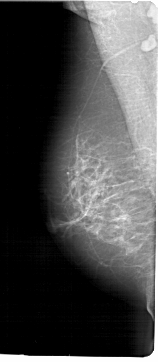

A_1424_1.LEFT_CC

LEFT_MLO LINES 6871 PIXELS_PER_LINE 2986 BITS_PER_PIXEL 12 RESOLUTION 43.5 NON_OVERLAY